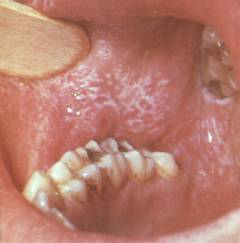

Поражение слизистых

Сначала на слизистой оболочке появляются небольшие серовато-белые папулы. Затем формируются бляшки, не имеющие восковидного оттенка из-за постоянного размягчения. Папулы могут объединяться, создавая кольца, сетки и другие узоры. Обычно они не вызывают боли и не сопровождаются симптомами, что отличает их от эрозивно-язвенной формы.